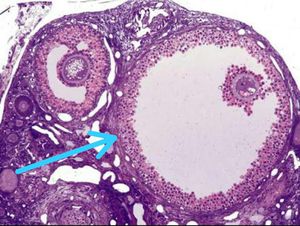

Identify the marked structure

Graafian follicle?

Antral follicle

Graafian follicle

Corona radiata cells of graffian follicle

Thecal cells of graffian follicle